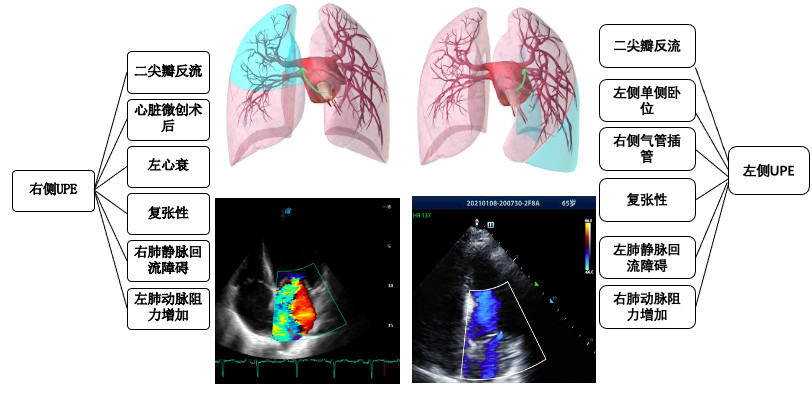

Mostafa等评估肺水肿影像评分(radiographic assessment of lung edema, RALE)诊断UPE的准确性[56]。将胸片分为4个向限,每个向限得分为实变严重程度(0分~4分)×模糊程度(1分~3分),每个向限总分12分,单侧肺总分24分。术后右侧分值大于12分,以及右侧-左侧分差大于13诊断UPE的敏感度和特异度分别为100%和94.4%,88.4%和94.2%(见图 2和表 2)。

| 图 2 肺水肿影像评分 |